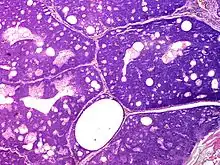

Sebaceoma (also known as a "sebaceous epithelioma") is a cutaneous condition that appears as a yellow or orange papule.[1]:662